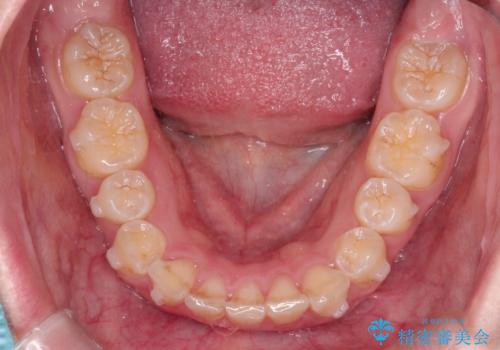

- 前歯のガタガタが気になるとのことで来院されました。

上顎の前歯の叢生があったのと、下あごの前歯が通常より1本欠損(先天欠損)していました。

上顎の歯と歯の間をわずかに削りスペースをつくり、並べる計画としました。インビザライン治療を選択されました。